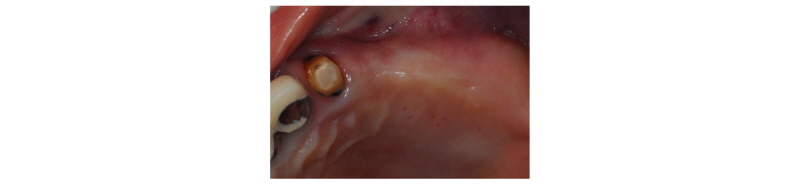

57세의 여성 환자로 기존 브릿지 보철 수복물(#24-27)의 상악 좌측 제 2대구치의 심한 우식으로 인해 내원하여 해당 치아를 발거하였다(Fig. 1). 상악 좌측 제 1 소구치는 근관치료를 시행한 후 보철 수복하기로 하였고 기존 pontic 부위였던 좌측 제 2 소구치와 발거된 제 2 대구치 부위에 #25i, #27i 2개의 임플란트 식립을 통한 브릿지 보철 수복물을 계획하였다(Fig. 2). 기존 pontic으로 유지되었던 좌측 제 2 소구치 부위는 치조제의 심한 수평적 치조골 흡수를 구강 내 임상검사를 통해 확인할 수 있었다. 전층 판막 형성후 상악 좌측 제 2 소구치 부위의 치조정 폭경은 약 2 mm 정도로 측정되었다(Fig. 3, 4). 치조골의 구개측에 약 1 mm의 치조골이 남도록 high speed carbide round bur를 이용하여 치조정에 horizontal intraosseous groove를 형성하였고 협측골의 근심, 원심측에 2개의 vertical intraosseous groove를 형성하였다(Fig. 5). Chisel과 ridge spreader drill (RS kit, Dentium, Korea)을 이용하여 점차적으로 협측 골판을 구개측으로부터 분리시켰다(Fig. 6). Osteotome을 이용, 식립 깊이까지 적용하여 임플란트 식립 부위를 형성하였고 Ø4.3 × 10 mm (Implantium, Dentium, Korea) 임플란트를 식립하였다(Fig. 7). 발치 후 치유된 상악 좌측 제 2 대구치 부위는 상악동 거상술(수직 접근법)을 시행, 골이식을 한 후 4.8 × 10 mm (Implantium, Dentium, Korea)를 식립하였다(Fig. 8). 이후 이종골 이식재(Bio-Oss®, Geistlich, Switzerland)를 식립된 임플란트와 협,구개 측 치조골판 사이의 gap과 협측골판 상방에 적용하고 흡수성 교원질 차폐막(Bio-Gide®, Geistlich, Switzerland)로 피개한 다음 감장절개를 통해 장력없이 봉합하였다(Fig. 9-11). 이후 구강 내 검사 및 방사선 검사를 통해 수술부위 치유상태를 확인하였고 특이한 임상적 소견없이 정상적으로 잘 치유되었다(Fig. 12). 약 3개월 10일 정도의 치유기간 후 이차수술을 시행하였다(Fig. 13). 판막 거상 후 치조제 분할술을 시행하였던 상악 좌측 제 2 소구치 부위에 잘 형성된 신생 골양조직이 관찰되었다(Fig. 14). 상악 좌측 제 2 소구치 부위와 상악 좌측 제 2 구치 부위에 치유지대주를 장착하였고 상악 좌측 제 1 대구치 부위에 추가적으로 임플란트를 1회법으로 식립하였다(Fig. 15). 이차수술 이후 정상적으로 치유가 진행되어 약 2개월 후 최종 보철물 수복을 하였다(Fig. 16, 17). 약 1년 정도의 follow-up시 구강 내 검사와 방사선 검사를 통해서 임플란트 주위 연조직과 변연골이 잘 유지되고 있음을 확인하였다(Fig. 18).

|

Fig. 3. Clinical view. Pre-op. |